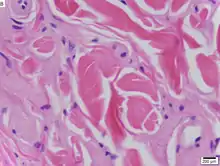

Urbach–Wiethe disease in skin biopsy with H&E stain. | |

The dermatological symptoms are caused by a buildup of a hyaline material in the dermis and the thickening of the basement membranes in the skin.[9] The nature of this material is unknown, but researchers have suggested that it may be a glycoprotein, a glycolipid, an acid mucopolysaccharide, altered collagen or elastic tissue.[6]